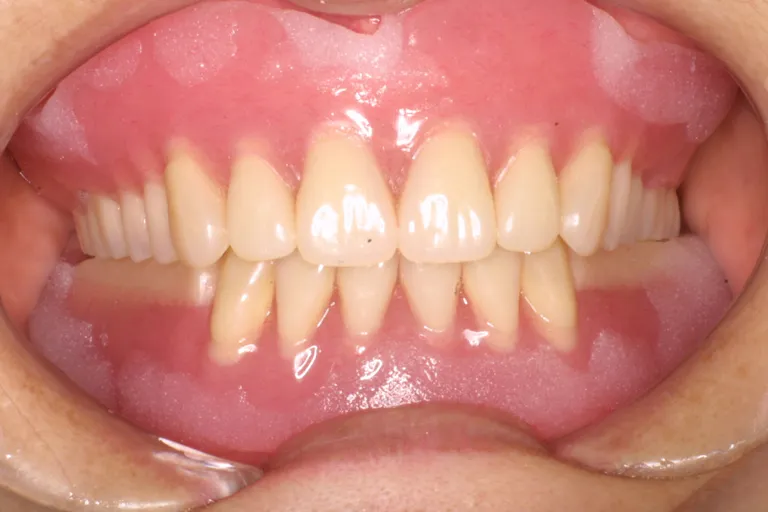

■術後の状態■しっかりと噛める強度と快適な装着感で外からは自然な見た目です

■術後の状態■

しっかり噛める

口腔環境にします